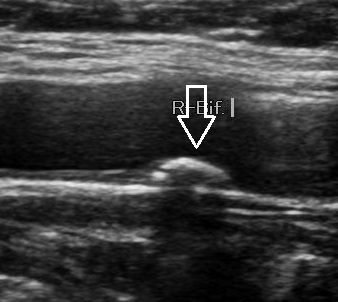

경동맥 협착증은 혈관 내벽에 콜레스테롤, 지방, 칼슘이 쌓여 혈관이 좁아지는 질환입니다. 경동맥 내경이 50% 이상 좁아지면 뇌혈류가 감소하여 뇌졸중 위험이 급격히 증가합니다. 초음파를 통해 협착 부위의 정도, 혈류 속도, 플라크의 성질(단단한지, 불안정한지)을 정밀하게 평가할 수 있습니다.

경동맥 초음파 검사는 준비 과정이 간단합니다. 공복 상태일 필요가 없으며, 목 주변의 금속 액세서리나 목도리만 제거하면 됩니다. 검사 시간은 약 10~20분 정도이며, 환자는 눕거나 고개를 약간 돌린 상태로 검사를 진행합니다. 탐촉자를 목 부위에 대고 초음파를 투사하면 화면에 경동맥의 단면이 실시간으로 나타나며, 의사는 혈류 속도와 벽의 상태를 분석합니다. 혈관이 막혀 있거나 좁아진 부분에서는 혈류 속도가 비정상적으로 증가하므로, 이를 통해 협착의 정도를 정량화할 수 있습니다.